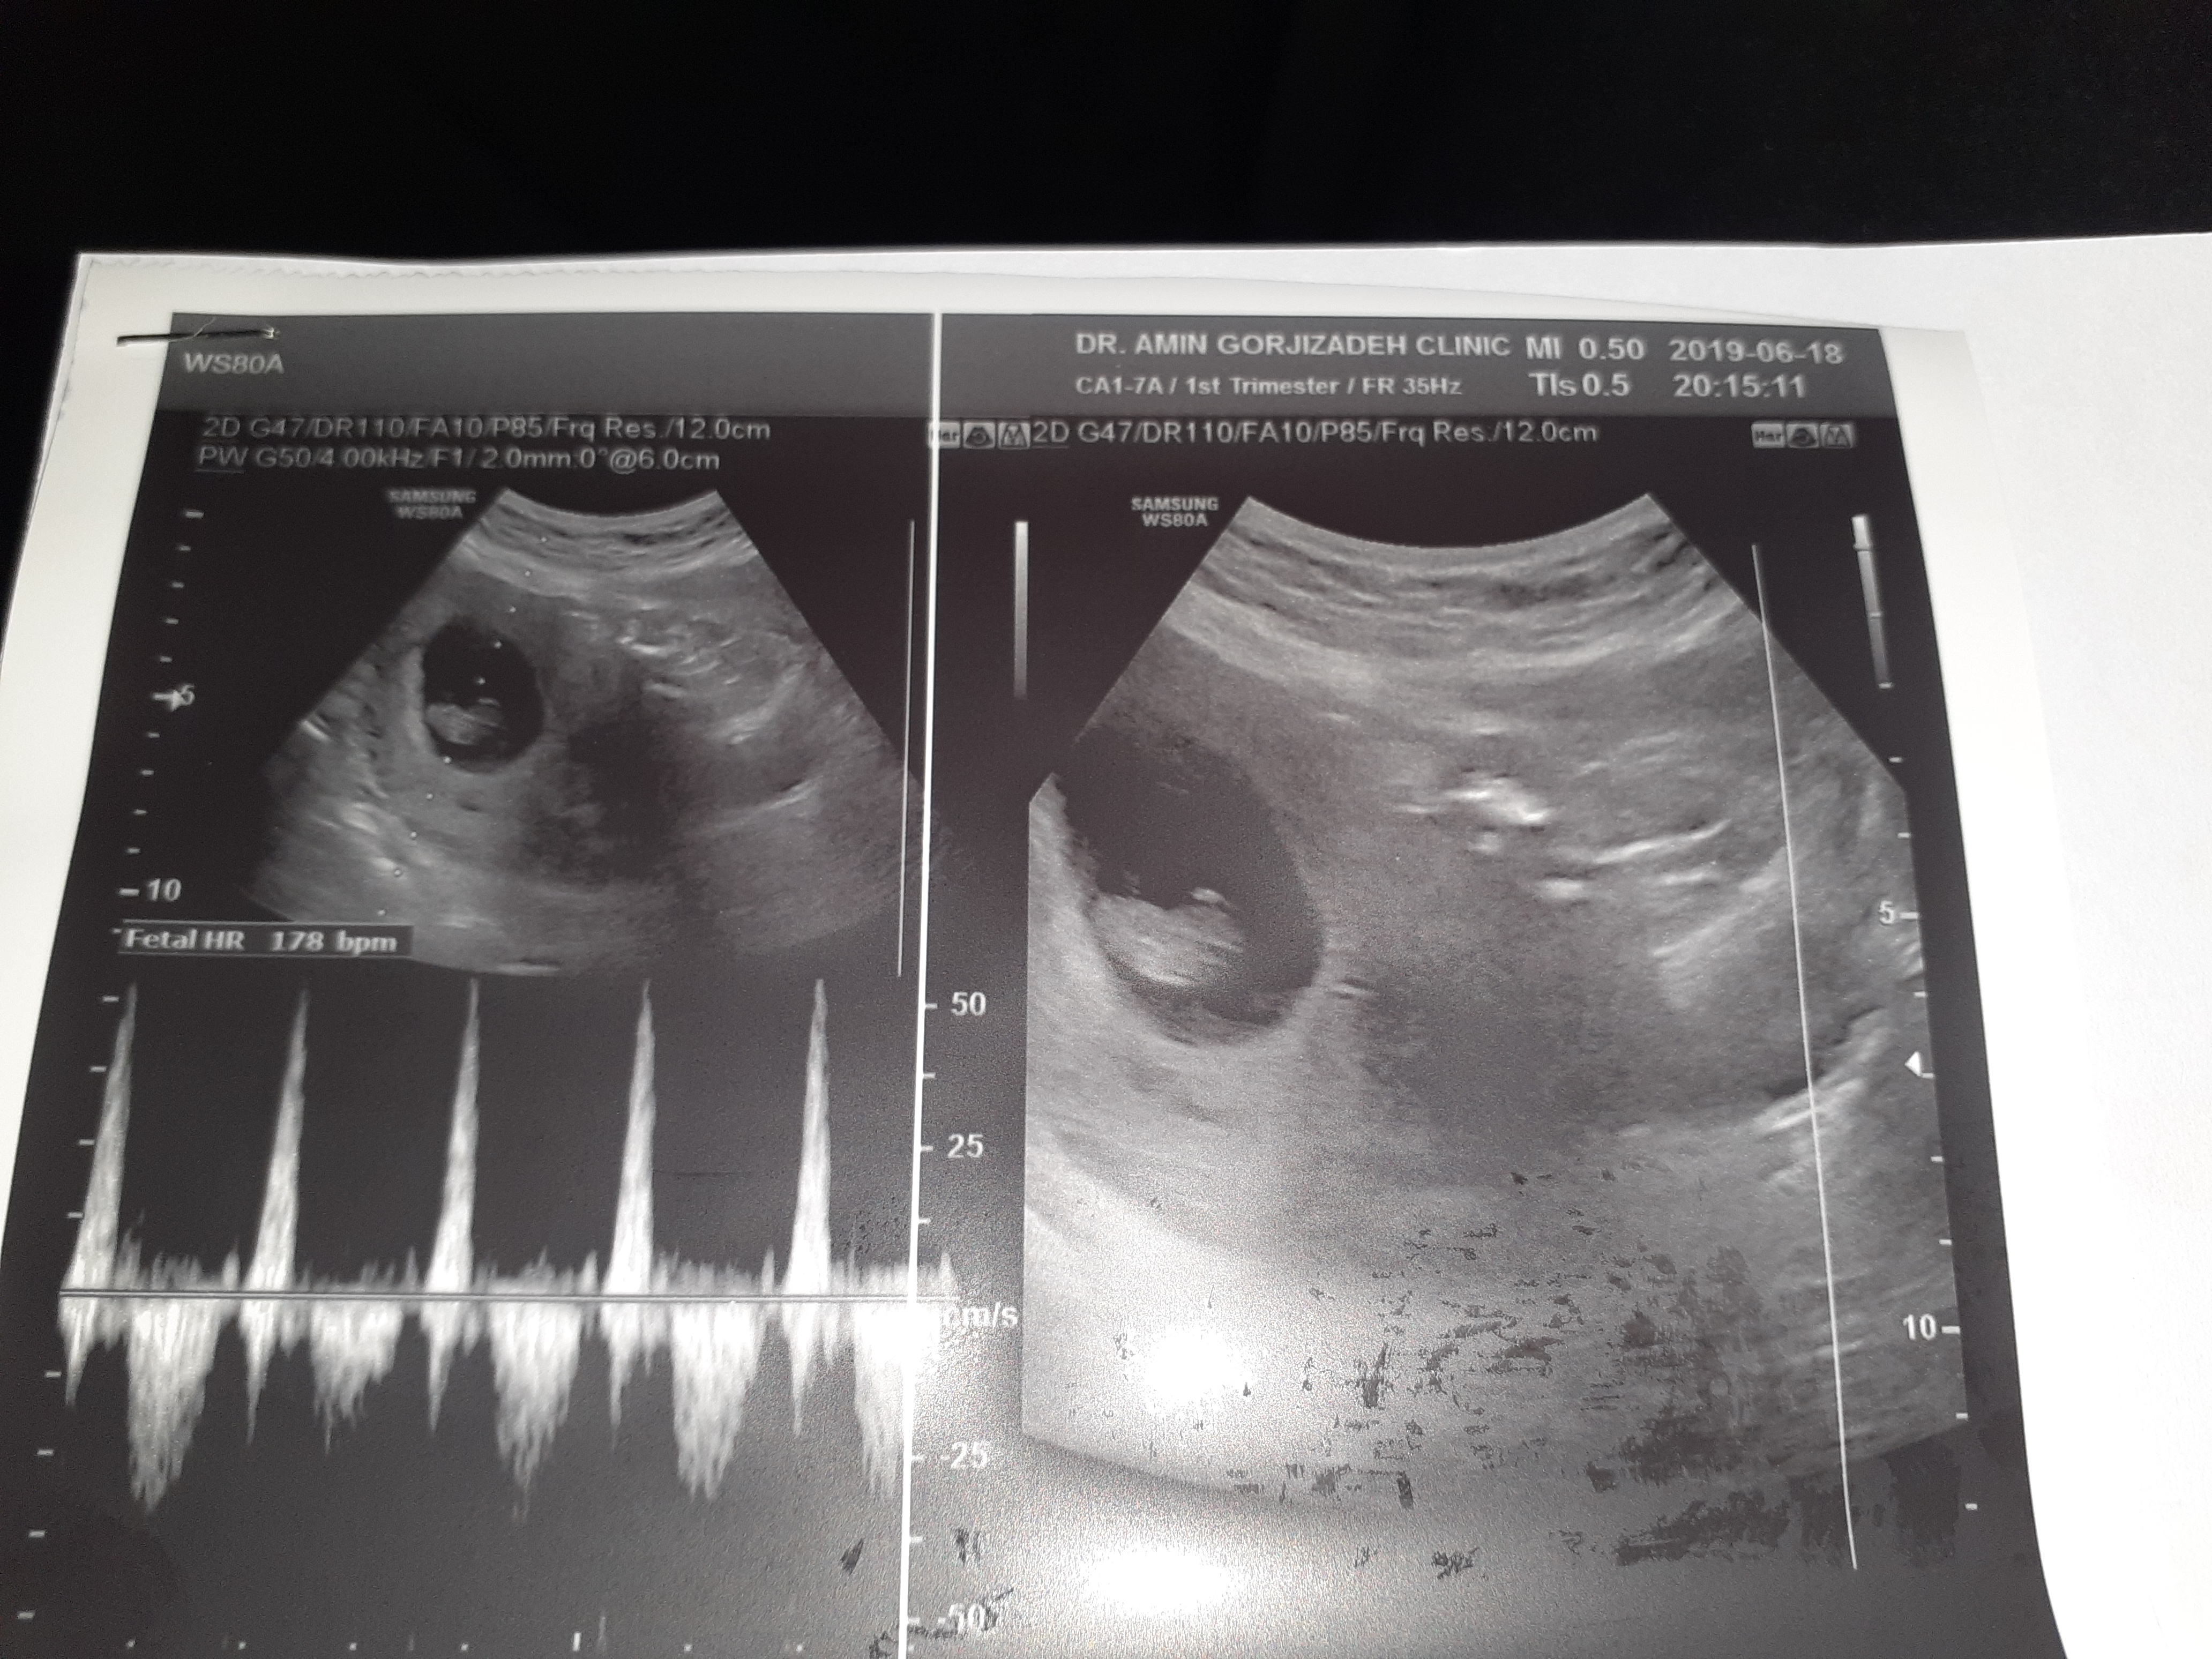

نی نی من ۸ هفته است می تونی حدس بزنی

چرا اتفاقا داره از ۱۴۰تا ۱۷۰دختره  و زیر ۱۴۰و بالای ۱۷۰پسره

برا من ۱۷۵ یعنی پسره 🤔

عزیزم ۸ هفته هنوز اندامشم تشکیل نشده گلم الان دنبال جنسیتش نباش